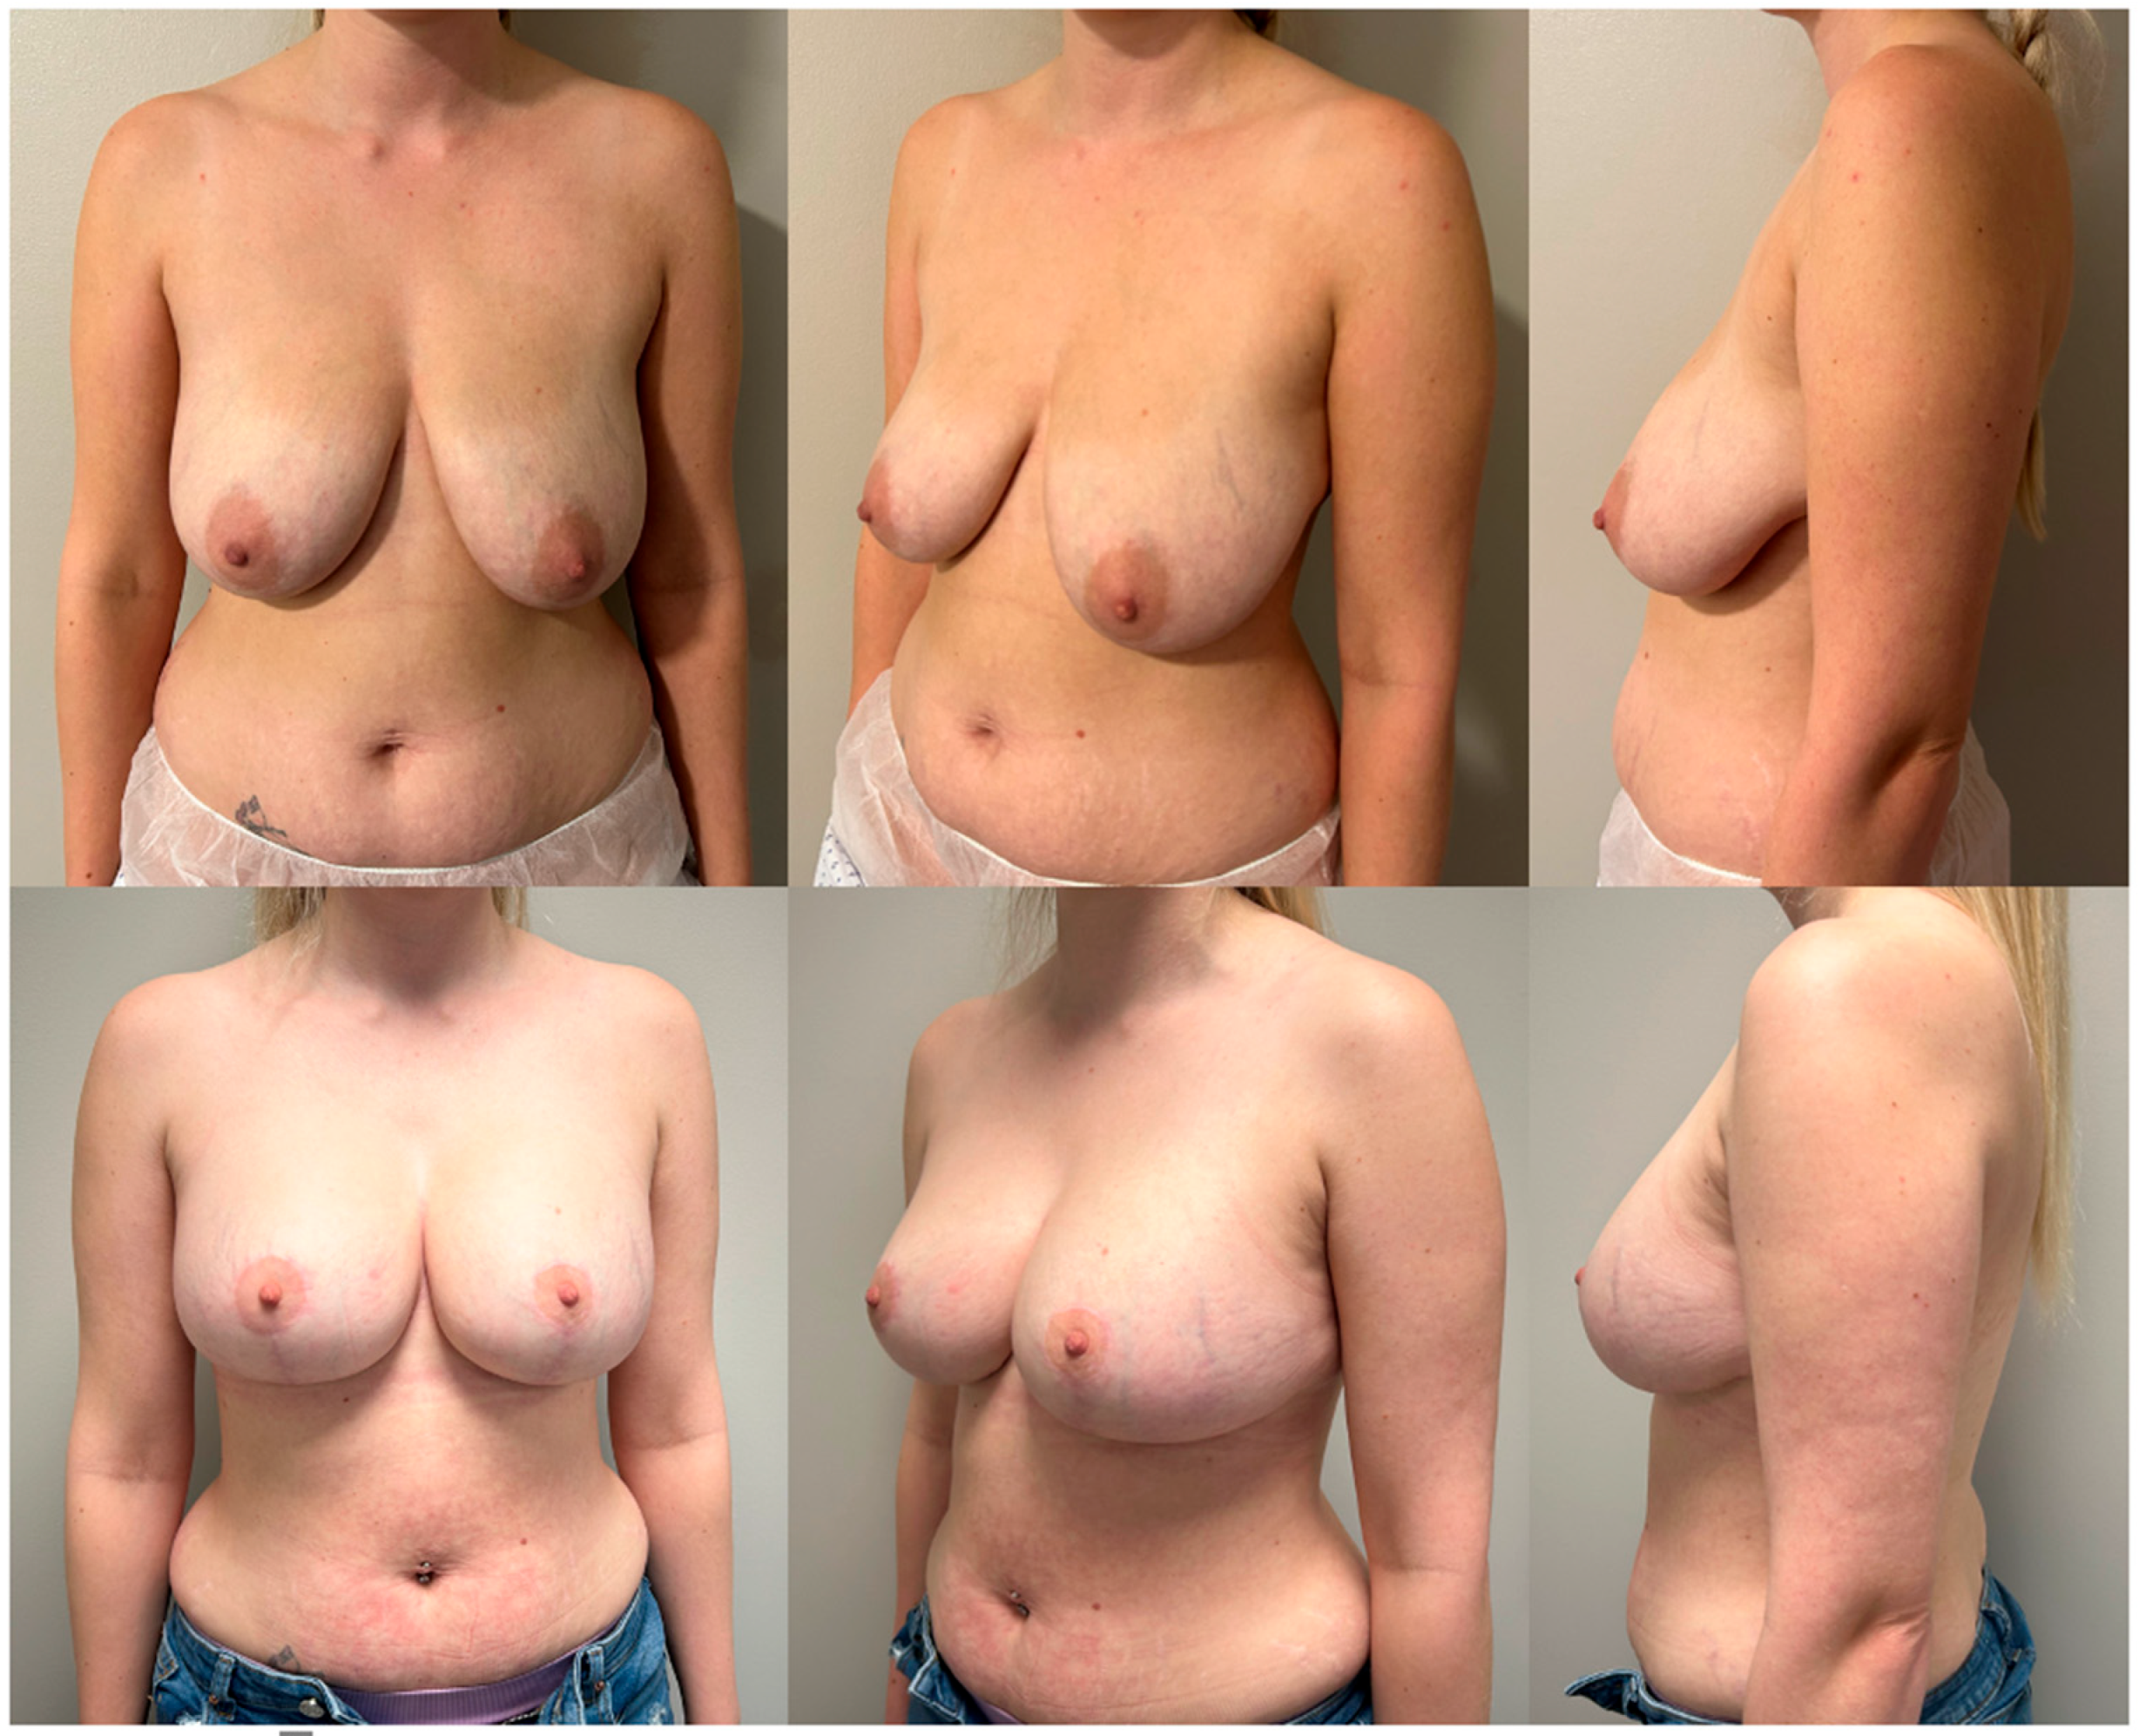

The findings from our pre-operative and post-operative questionnaires show that patients, overall, reported a statistically significant improvement in satisfaction across all six question parameters (

Table 2). This supports the effectiveness of breast reduction plus implants in attaining an outcome desired by patients (

Figure 1 and

Figure 2).